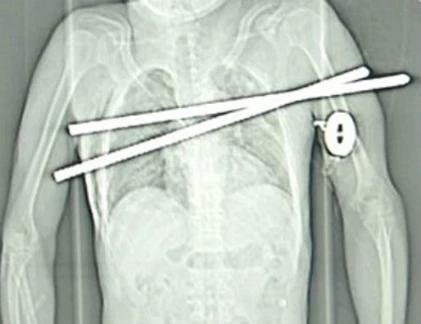

Một trường hợp khác cũng là người đàn ông Trung Quốc thoát nạn, hồi tháng 8/2011, người thợ xây may mắn này đang làm việc ở một công trường tại thành phố Đại Liên, tỉnh Liêu Ninh, thì ngã trúng 2 thanh sắt được sử dụng để gia cố bê tông. Thật kinh ngạc, người đàn ông vẫn sống sót khi 2 thanh sắt đâm xuyên qua ngực nhưng may mắn không trúng tim, phổi và xương sống.